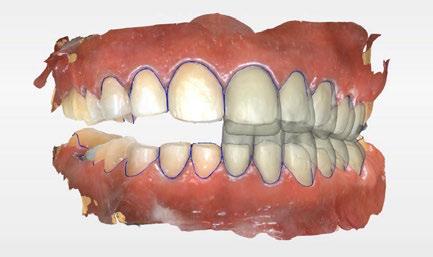

Se obtuvieron modelos de estudio (Figuras 3-6) digitales mediante un escáner confocal de luz azul estructurada (PrimeScan, Dentsply Sirona) y se planificó un protocolo de desgaste mínimamente necesario y conservador de las estructuras

dentarias, cumpliendo parámetros biológicos, terapéuticos, mecánicos y estéticos. Después se realizó un modelado digital retrospectivo (Figuras 7-11) para generar modelos impresos 3D para realizar el mock up funcional, estético y como guía para las preparaciones (Figuras 12-15). Con ello, se efectuaron las preparaciones dentarias y los registros intermaxilares y, posteriormente, se digitalizaron ambos maxilares (Figuras 16-21)

Terminada esta fase se elaboró una propuesta de diseño (CEREC,

SW 5.2, Dentsply Sirona) (Figuras 22-27), la cual fue materializada en dos tipos de materiales a partir de bloques cerámicos IPS Empress CAD y cerámica vítrea de disilicato de litio IPS E.max CAD (Figuras 28-30)

Figura 7. Modelado digital. Figura 9. Propuesta de diseño en oclusión Figura 10. Vista lateral derecha. Figura 8. Propuesta de diseño arcada superior. Figura 11. Vista oclusal superior del modelado. Figura 12. Mock Up impreso en oclusión. Figura 14. Mock Up que evidencia el desgaste dentario en el maxilar inferior.